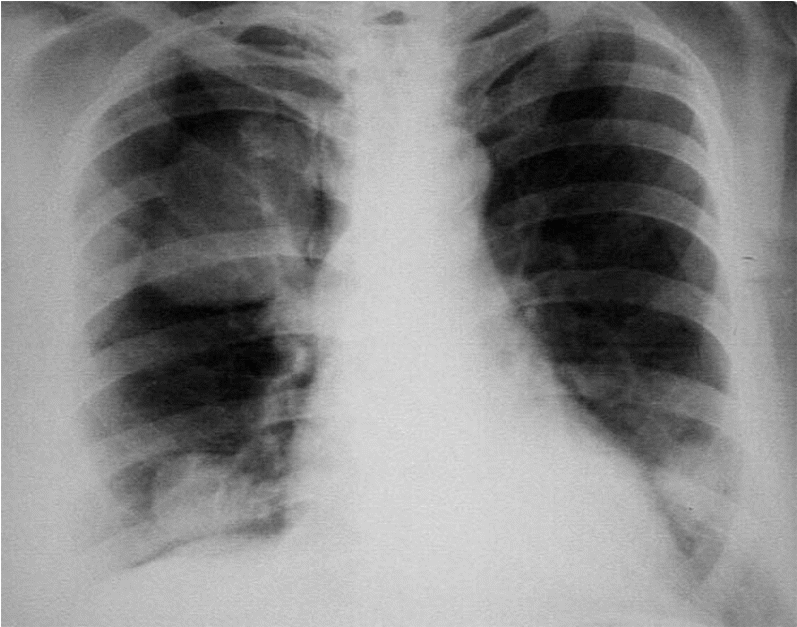

Ч

аще

всего метастазирование опухолевых

клеток происходит гематогенным или

лимфогенным путем. Метастазы обнаруживаются

у 25% пациентов на момент установления

диагноза. Выживаемость данных больных

составляет от 6 до 12 месяцев и только

10% переживают 2 года. Приблизительно у

30-50% больных в различные сроки после

нефрэктомии появляются метахронные

метастазы. Прогноз последней группы

несколько лучше, однако 5-летняя

выживаемость не превышает 9%. Наиболее

частыми локализациями множественных

метастазов являются легкие

76%, лимфатические узлы

64%, кости

43%, печень

41%, ипсилатеральный и контралатеральный

надпочечники

19% и 11,5%, контралатеральная почка

25%, головной мозг

11,2% (рис. 19-23). Солитарные метастазы или

метастатическое поражение только одного

органа имеет место только в 8-11% случаев.

Рис.22. Рентгенография. Метастазы в легкие при раке почки.